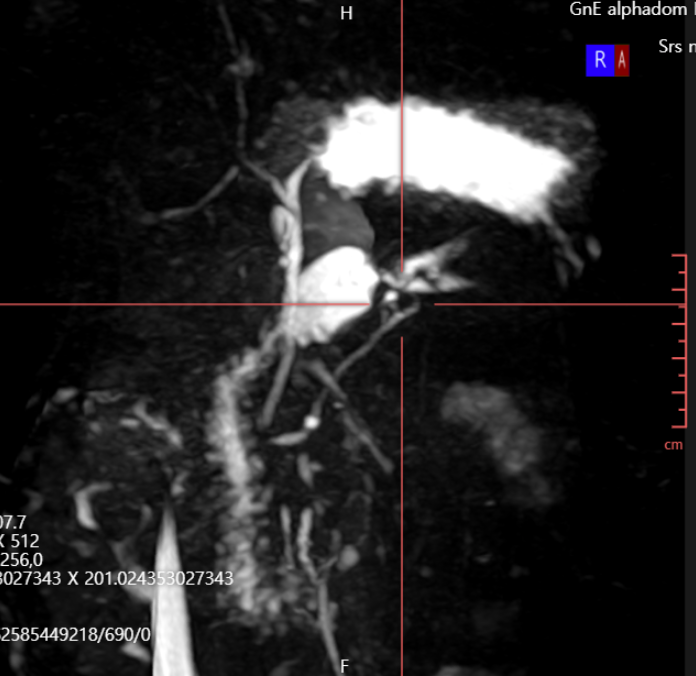

• 췌장MRI 3D촬영: 췌장낭종 확인 췌장MRI 3D촬영: 췌장낭종 확인

췌장몸통 쪽으로 약 0.8cm 가량의 물혹이 보이며, 이는 췌장담도와 연결성이 보이고 있습니다. 이는 췌관내유두점액낭종으로 생각이 되며, 이에 대해서 6개월 간격으로 추적 관찰을 하기로 했으며, 경과를 보고 치료시기를 결정하기로 했습니다.